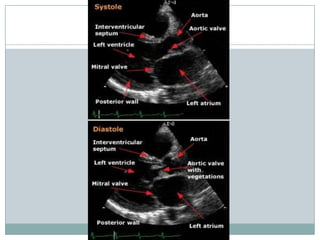

Diagnostic criteria for vegetations

** Valvular vegetation is defined as "a discrete mass of echogenic material adherent at

some point to a leaflet surface and distinct in character from the remainder of the

leaflet" based upon the following characteristics:

Texture — gray scale and reflectance of myocardium

Location — upstream side of the valve in the path of the jet or on prosthetic material

Characteristic motion — chaotic and orbiting; independent of valve motion

Shape — lobulated and amorphous

Accompanying abnormalities - abscess and pseudoaneurysm, fistulae, prosthetic

dehiscence, paravalvular leak, significant preexisting or new regurgitation

** Vegetations also characteristically prolapse into the upstream chamber: mitral

vegetations into the atrium in systole and aortic vegetations into the left ventricular

outflow tract during diastole.

**Vegetations tend to flank the regurgitant jet.